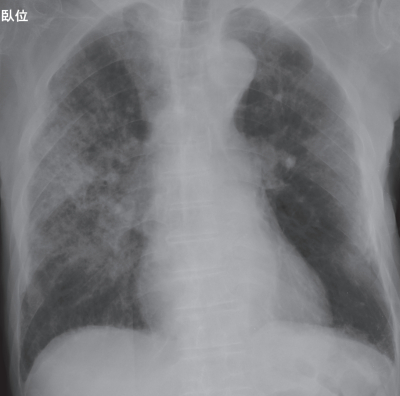

入院時の胸部エックス線写真と胸部単純 CTを別に示す。